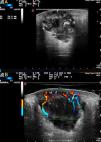

A, Heterogeneous polylobulated solid-cystic lesion in the dermis and extending into the subcutaneous tissue, coinciding with the histologic image; note the sparing of the superficial area of the dermis. B, Power Doppler imaging showing abundant peripheral vascularity penetrating the lesion from several poles.

A 55-year-old woman who had smoked since the age of 20 years and had no known diseases or drug allergies was under follow-up at the general surgery department for a painful lesion of 2 months’ duration on the right buttock that had grown despite 2 cycles of oral antibiotics prescribed by her primary care physician. The clinical diagnosis was an infected epidermal cyst and the lesion was drained in the general surgery department. Despite follow-up care over a month, the wound did not heal and the patient was referred to us for evaluation. Physical examination showed an erythematous-violaceous indurated plaque with a 5-cm diameter on the upper outer quadrant of the right buttock (Fig. 1). The plaque, which was hard on palpation, contained an ulcer measuring 15mm at its widest diameter secondary to the surgical drainage. The central area of the ulcer was very deep and its walls contained a solid yellowish-white material. When questioned, the patient reported that she had lost 15kg in 2 months, a loss that she attributed to a naturopathic diet. We examined the lesion by ultrasound and performed a wedge biopsy for histologic and microbiologic studies. The fungal, bacterial, and mycobacterial cultures were all negative. Color Doppler imaging on a MyLabClass C machine (Esaote) equipped with an 18-MHz probe revealed a heterogeneous solid-cystic lesion measuring 45×27mm in the dermis and extending into the subcutaneous tissue. The lesion also had anechoic central areas admixed with hyperechoic areas with well-defined borders (Fig. 2). It displayed posterior reinforcement and Power Doppler imaging showed peripheral vascular poles. The above findings (the heterogeneity and significant vascularity at several poles of the lesion) suggested malignancy, which allowed us to request a rush histology study. Histologic examination showed infiltration of the dermis by a malignant epithelial proliferation of cells with a squamous pattern of growth, marked nuclear pleomorphism, prominent nucleoli, and several mitotic figures; the proliferation formed solid nests with evident intercellular bridges and apoptotic cells (Fig. 3 A and B). There was also extensive necrosis and no signs of connection with the epidermis. The proliferation extended as far as the peripheral and deep borders of the biopsy specimen. With a diagnosis of poorly differentiated squamous cell carcinoma, we requested a chest radiograph, which showed a nodule in the left lung and a focal interstitial infiltrate containing septal lines and images of nodules in the right lung. Positron emission-tomography-computed tomography confirmed the presence of a disseminated stage IV lung tumor with a large pulmonary mass in the right upper lobe and multiple lung and bone metastases. The study also showed a hypermetabolic soft tissue mass corresponding to the skin lesion on the right buttock. The patient opted to have the lesion completely excised. She was enrolled in a palliative care clinical trial by the oncology department, but died 7 months later.

High-frequency ultrasound is a fast, affordable, noninvasive technique that can strongly predict malignancy in cases of cutaneous metastasis. Very few articles have been published on ultrasound studies of cutaneous metastases from tumors other than melanoma.3,9,10 Giovagnorio et al.3 found that a polycyclic shape and hypervascularity with multiple peripheral poles were indicative of cutaneous metastasis. The differential diagnosis should include inflamed epidermal cysts, cutaneous lymphomas (which can be accompanied by considerable inflammation), and cystic areas in patients with hidradenitis suppurativa. In this last case, sinus tracts and drainage sinuses will be observed both clinically and by ultrasound.